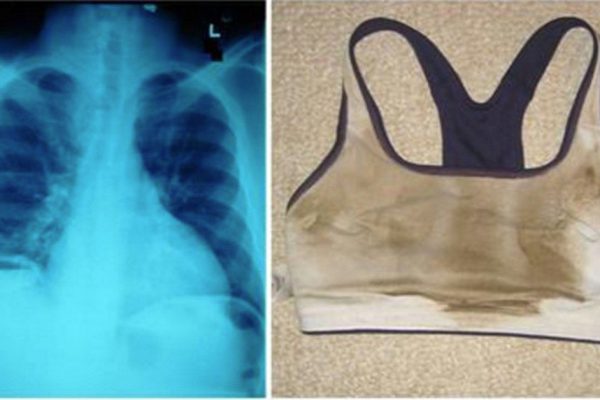

Осторожно! Нынче в общественном транспорте гуляют страшные инфекции… Защити себя!

Жизнь в городе сопряжена со множеством опасностей, и одна из главных – инфекции. В холодное время года любой, кто оказался в транспорте — потенциальная жертва ОРВИ, а туберкулез вообще опасность внесезонная. Но так ли всё страшно, как об этом повсюду […]